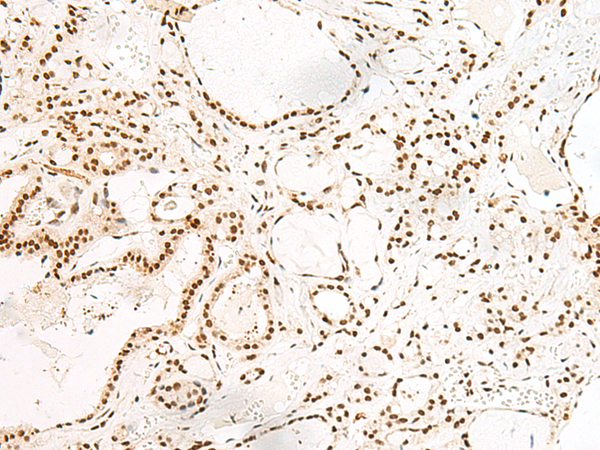

IHC positive control: |

Human esophagus cancer and Human thyroid cancer |